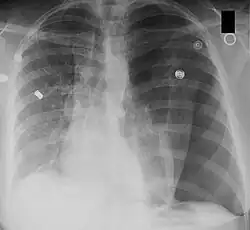

Post-operative changes

A pneumonectomy is a surgical procedure in which an entire lung is removed. A common reason for performing this procedure is for lung cancer originating in the lung itself.[19] This leads to a mediastinal shift towards the empty side of the thorax. Notably, patients can experience post pneumonectomy syndrome due to a severe mediastinal shift. This presents as difficulty breathing due to a shift of airways and rotation of the heart and great vessels. On x-ray, white out of the operated side and hyperinflation of the remaining lung is often observed.[20]